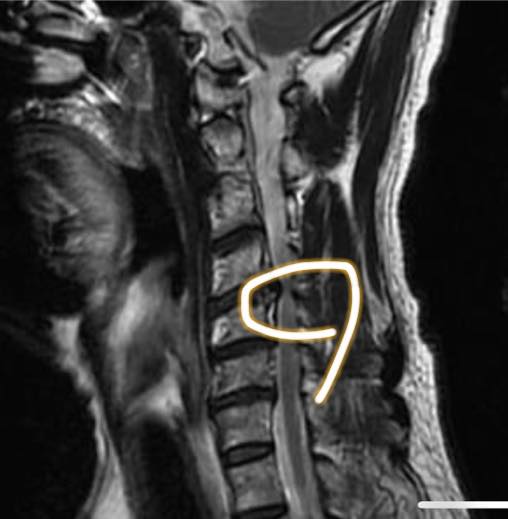

Cervical Spine Treatment Cases 頸椎治療案例 #疼痛三年頸椎病患者親手寫下治療紀錄 #交感神經型頸椎病 #症狀錯綜複雜 2020.10.02 #困擾四年多胸悶手麻頭暈醫案 #一切原因居然是頸椎出問題 #交感神經型頸椎病症狀錯綜... 2020.09.11 #交感神經型頸椎病引起的耳鳴 #耳鳴將近八個月終於得到重大改善 #曾經耳鳴到無法睡覺... 2020.08.22 #感謝板橋蘇先生熱情見證 #神經根型頸椎病卡壓 #曾痛痛到左手無法騎單車撥桿 #麻脹刺... 2020.08.04 #後縱韌帶鈣化引起椎管狹窄 #痛到完全無法睡覺長達半年以上 #原本已經準備開刀最後逆... 2020.07.16 #牽一頸而動全身的特殊醫案 #兩分鐘瞭解交感神經型頸椎病 #絕望的黑暗人生看到一絲希... 2020.07.03 #長達七年的頸椎疼痛是怎麼回事 #神經根型頸椎病 #低頭族跟家庭主婦辛苦了 #逆轉勝醫... 2020.07.01 #頸椎整合中醫微創療法 #感謝新竹黃大哥熱情見證 #逆轉勝成真醫案 2020.06.25 #頸椎病手術後也要要好好保健 #毛巾操很重要再度上場 #感謝某大醫學中心主任見證 2020.06.24 #這些症狀很可能都是頸椎出問題 #患者看七種不同科別醫師找不出原因 #交感神經型頸椎... 2020.06.09 #消失的頸椎曲線能夠回來嗎? #核磁共振前後對比椎管容積打開 #脊椎整合中醫微創療法❤... 2020.06.05 #感謝新竹薛大哥熱情見證 #頸椎整合中醫微創療法 治療:4/21~5/30(八次) 效果顯著... 2020.05.30 從宜蘭來的游小姐患者熱情見證 頸椎整合中醫微創療法 逆。轉。成。真。 2020.05.29 #脊髓型頸椎病案例 2020.05.26 #感謝新北市黃小姐熱情見證 #疼痛時間超過一年 #晨起麻痛到不行的日子長達半年以上 #... 2020.05.16 ← 上一頁 5 6 7 8 9 下一頁 →